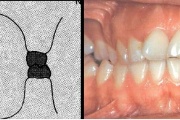

Valehambumus

Hammaste asendianomaaliad on tingitud tavaliselt arenguhäirest.

(18)